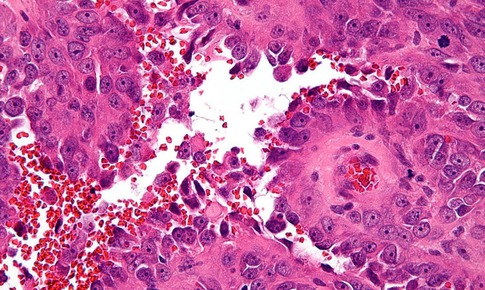

Ung thư - 12/10/2025 10:58SKĐS - Ung thư nội mô mạch máu có thể xuất hiện ở nhiều vị trí hiếm gặp như tim, xương hay ruột, khiến chẩn đoán và điều trị trở nên khó khăn, dễ bị phát hiện muộn.